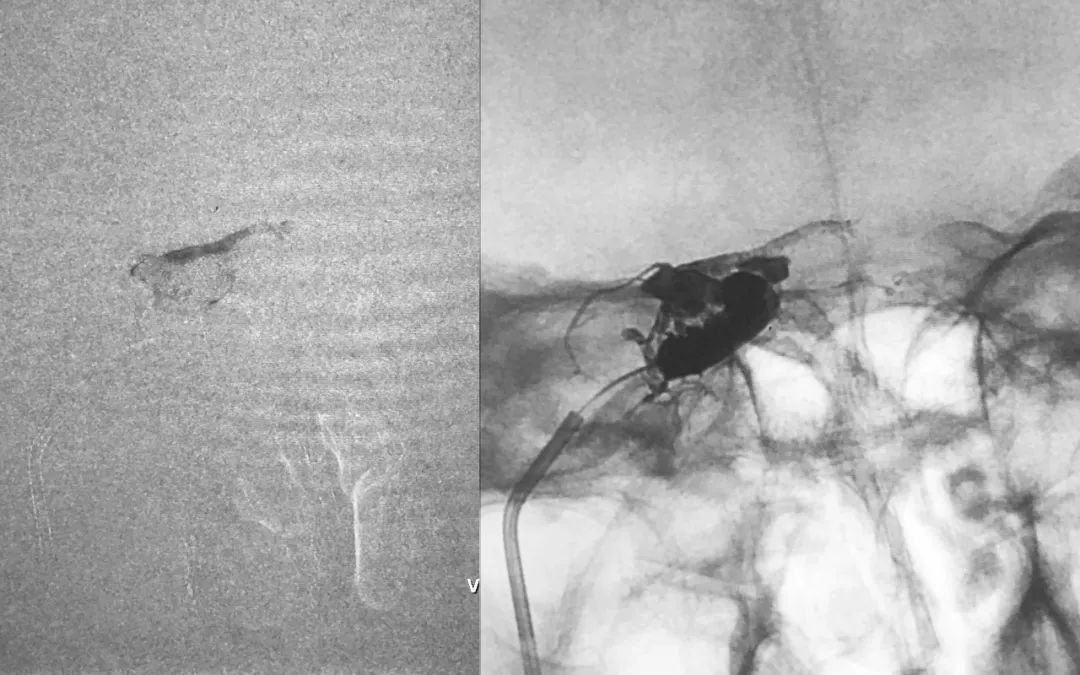

④ 侧位微量路图指示下,经Echelon-10微导管向右侧眼上静脉根部送入3枚弹簧圈(APB-5-15-3D-SS,PC-3-6-3D,PC-3-6-3D),以限制胶的过度弥散:

⑤ 侧位空白路图下,经微导管缓慢、间歇注射Onyx-18胶:

正、侧位蒙片显示Onyx-18胶在右侧海绵窦内的铸型(约4.5 mm):